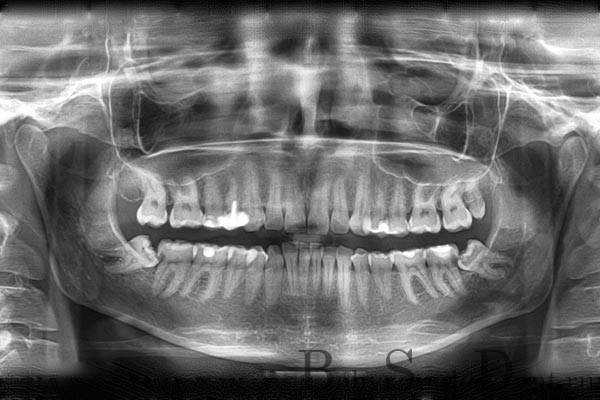

Дентальные снимки и диагностика кариеса